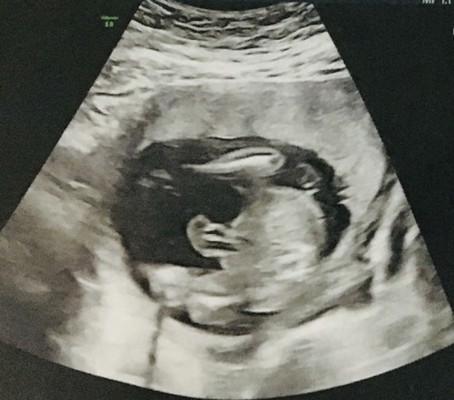

20วีคแล้วคะแม่ๆๆช่วยดูทีคะ แบบนี้ชายหรือหญิงคะ